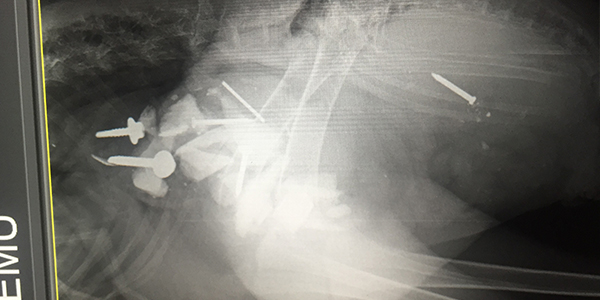

X-Ray of Emu showing foreign bodies ingested

Emergency surgery was performed on the Emu at RSPCA Queensland's Wildlife Hospital at Wacol, to remove metal objects from his stomach.

RSPCA Veterinarian Dr. Meghan Burrows performed the 2.5 hour surgery on “Digger” and says he’s extremely lucky.

“The Emu had ingested the foreign objects some time ago and as a result they had caused significant damage to the bird,” she said.